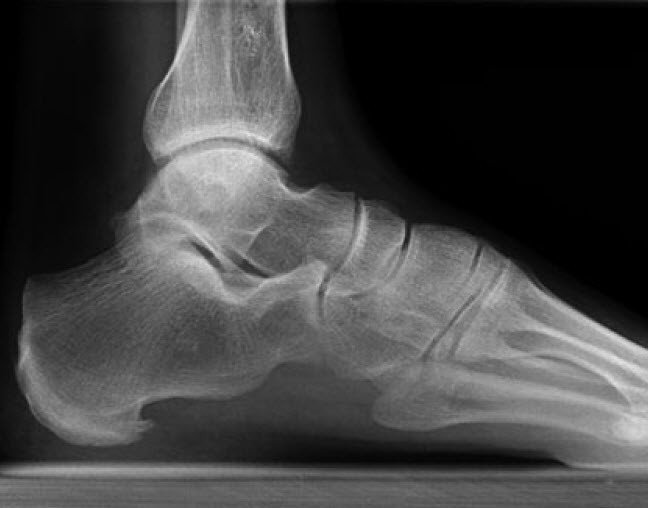

Haglund-Ferse

Mit diesem Begriff werden Entzündungen an der Rückseite der Ferse umschrieben. Im Röntgenbild erkennt man häufig einen knöchernen Vorsprung. Ursache der Schmerzen sind entzündliche und / oder degenerative Veränderungen am Achillessehnenansatz oder eine Schleimbeutelentzündung.

Die Beschwerden treten bei Belastung und beim Anlaufen auf. Häufig bereitet das Tragen geschlossener Schuhe aufgrund der lokalen Druckausübung Probleme.